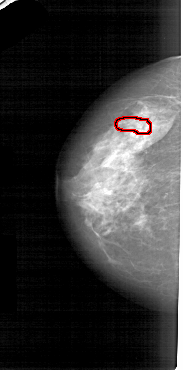

A_1553_1.RIGHT_CC

FILE: A_1553_1.LEFT_CC.OVERLAY

TOTAL_ABNORMALITIES 1

ABNORMALITY 1

LESION_TYPE CALCIFICATION TYPE PUNCTATE DISTRIBUTION LINEAR

ASSESSMENT 4

SUBTLETY 1

PATHOLOGY BENIGN

TOTAL_OUTLINES 1

BOUNDARY